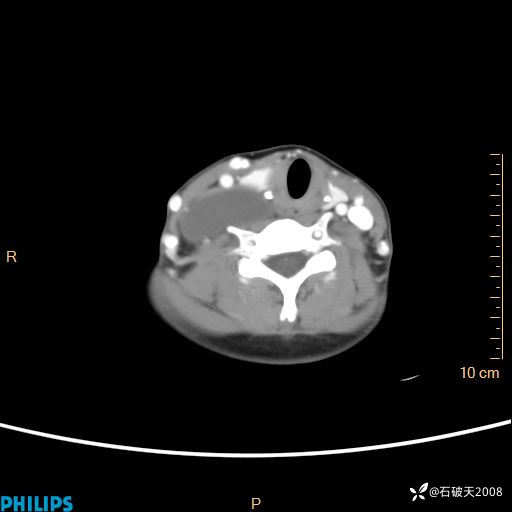

影像诊断要密切结合临床,真的很有必要(病理已公布)

女 21岁 主 诉:发现右侧颈部肿物18年余。

现病史:18年余前患者无明显诱因发现颈部偏右侧有一肿物,具体大小不明确,咳嗽、憋气时肿物增大,局部无疼痛,无吞咽不适,无胸闷及呼吸困难,至当地医院检查考虑良性病变(具体不详)并未做特殊处理,现患者自觉肿物随年龄增长而进一步变大,今日至我院行颈部CT平扫+增强提示:1.右侧颈根部、锁骨上窝及纵隔内异常密度影,考虑良性病变,淋巴管瘤?囊肿?请结合临床。2.双侧颈部小淋巴结。建议结合临床及其他相关检查。现为行进一步治疗,门诊以“颈部局部肿物”为诊断收住我科,发病来患者神志清,精神可,饮食睡眠可,大小便正常,体重无下降。

冠状位